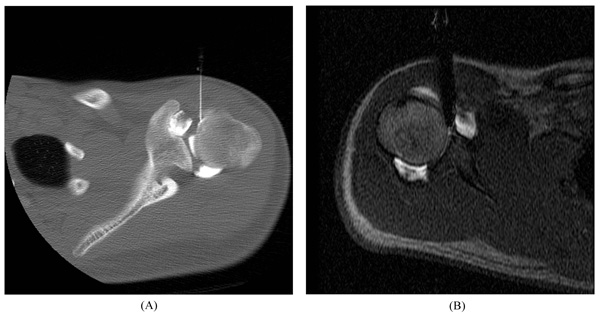

Fig. (1)

Arthrogram procedure. Anterior approach of needle for image-guided glenohumeral joint injection of contrast material using (

A

) CT and (

B

) MRI.